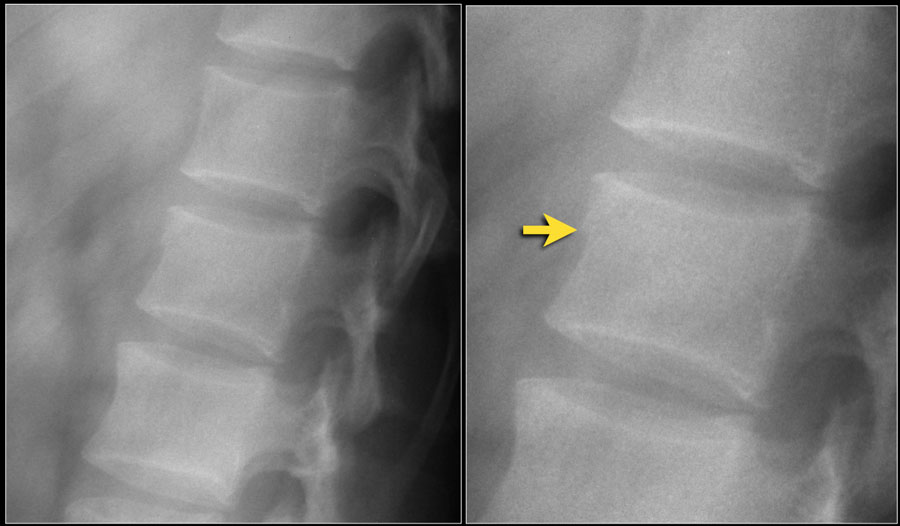

Рентгеновские снимки и медицинские изображения компрессионных переломов